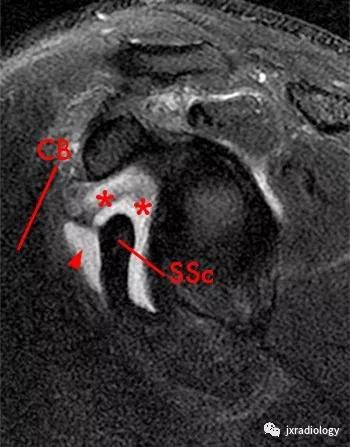

图2:肩胛下肌上隐窝(滑囊)( superior subscapularis recess)和

喙突下滑囊(subcoracoid bursa)

星号:superior subscapularis recess:肩胛下肌上隐窝

箭头:subcoracoid bursa:喙突下滑囊

SSc:肩胛下肌腱

小箭:middle glenohumeral ligament :盂肱中韧带